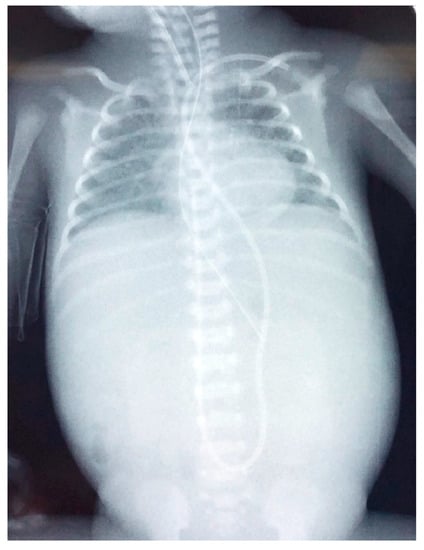

Figure 3.

Radiography of the neonate on the day of deterioration. Non-specific signal characteristics in the abdomen, such as distention and poor distribution of bowel gas. A clavicular fracture clavicle is noted on the right (red arrowhead).

Figure 6.

Radiography of the infant on the day of deterioration, with non-specific signal characteristics in abdomen, such as distended abdomen and poor distribution of bowel gas.

Figure 9.

(a) Chest and abdominal radiography depicting the abnormal position of umbilical venous catheter in the liver (red arrowhead); and (b) chest and abdominal radiography depicting air in the branches of right portal vein and hepatic parenchyma (red arrowhead).